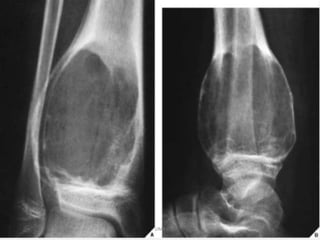

Osteochondroma. On this lateral view of the ankle, a

benign osteochondroma is seen projecting posteriorly

on a stalk. The end (arrows) is often covered with a

cartilaginous cap. These lesions always occur near a

joint but point away from it.UMY